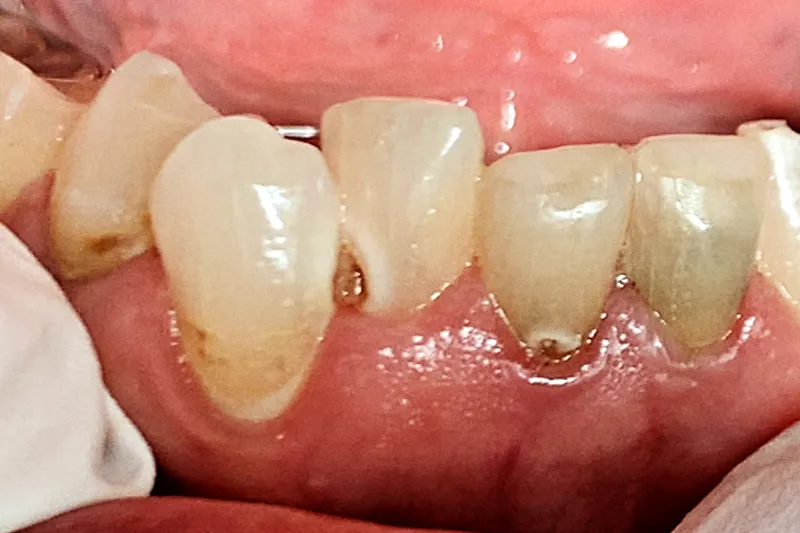

A735 figur 2

Patienttilfælde – Patienttilfældet omhandler en 69-årig kvinde, der får problemer med rygsmerter og herefter udvikler en række følgesygdomme, der fører til polyfarmaci. Sidstnævnte fører til udtalt xerostomi og hyposalivation, orale gener og sygdom, vægttab, social isolation, nedtrykthed, svækkelse og forringet livskvalitet.

Case study – This case describes a 69-year-old woman who develops problems with back pain and then develops a series of comorbidities that lead to polypharmacy. The latter results in pronounced xerostomia and hyposalivation, oral discomfort and disease, weight loss, social isolation, depression, weakness, and reduced quality of life.